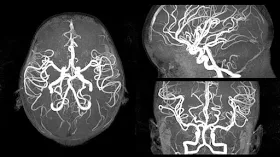

МРТ (или магниторезонансная томография) - один из методов обзора и анализа, который основан на использовании радиоволн и магнитных волн, а также компьютера, который преобразовывает изображение. МРТ в центре

При запуске томографа создаётся магнитное поле, которое постепенно начинает выстраивать протоны атомов водорода в один пучок радиоволн. Сегодня именно МРТ является наиболее точным способом обследования, поэтому многие врачи рекомендуют использовать МРТ для обследования, поскольку это позволит поставить более чёткий диагноз. Также вы можете пройти МРТ в Новосибирске. Для этого посетите диагностический центр "Альбамед" и вы получите качественное обследование, после которого увидите все изменения в вашем позвоночнике.

- Позволяет увидеть спинной мозг, а также нервы вокруг него;

- Видны все нервные окончания организма (позволяет диагностировать даже паралич);